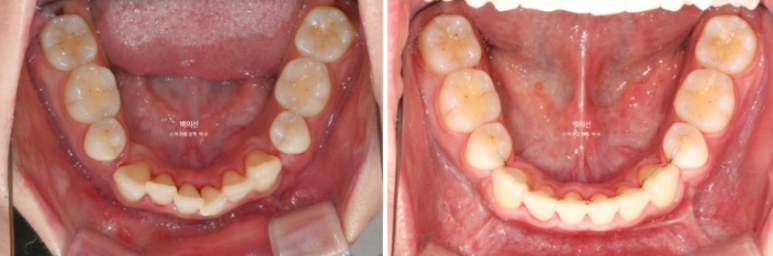

돌출입 수술을 하면 수술 테크닉적으로 작은어금니가 있던 공간이 약 2mm 이상이 남게 됩니다.

송곳니 뒤쪽에 2mm 의 공간이 각각 남았습니다.

이렇게 애매하게 남은 공간을 앞니 배열을 위한 공간으로 사용하는 것이 돌출입 수술교정의 핵심입니다.

전 후 비교 보겠습니다.

24.10~25.08

남아있던 공간은 추가장치로 깔끔히 없어졌습니다.